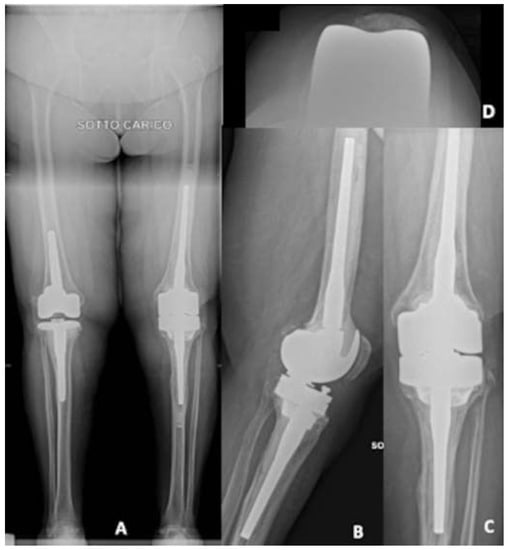

In this case, the 3D-printed model turned out to be extremely useful to plan the surgery. Considering knee dimension and the need for a constraint, the only implant that could fit these characteristics was the extra-small size of Endomodell® (Waldemar Link GmbH, Hamburg, Germany), which guaranteed both the right level of constraint and a very small dimension. With all this information, an accurate pre-operative planning, sizing, and surgery simulation was performed (Figure 4).

Post-operative X-rays for this patient are shown in Figure 5.

Six months after surgery, the patient was satisfied with complete ROM, stable knee, no pain and no sign of loosening at the X-rays.

Figure 5. Post-operative X-ray. (A) Antero-posterior view; (B) lateral view.